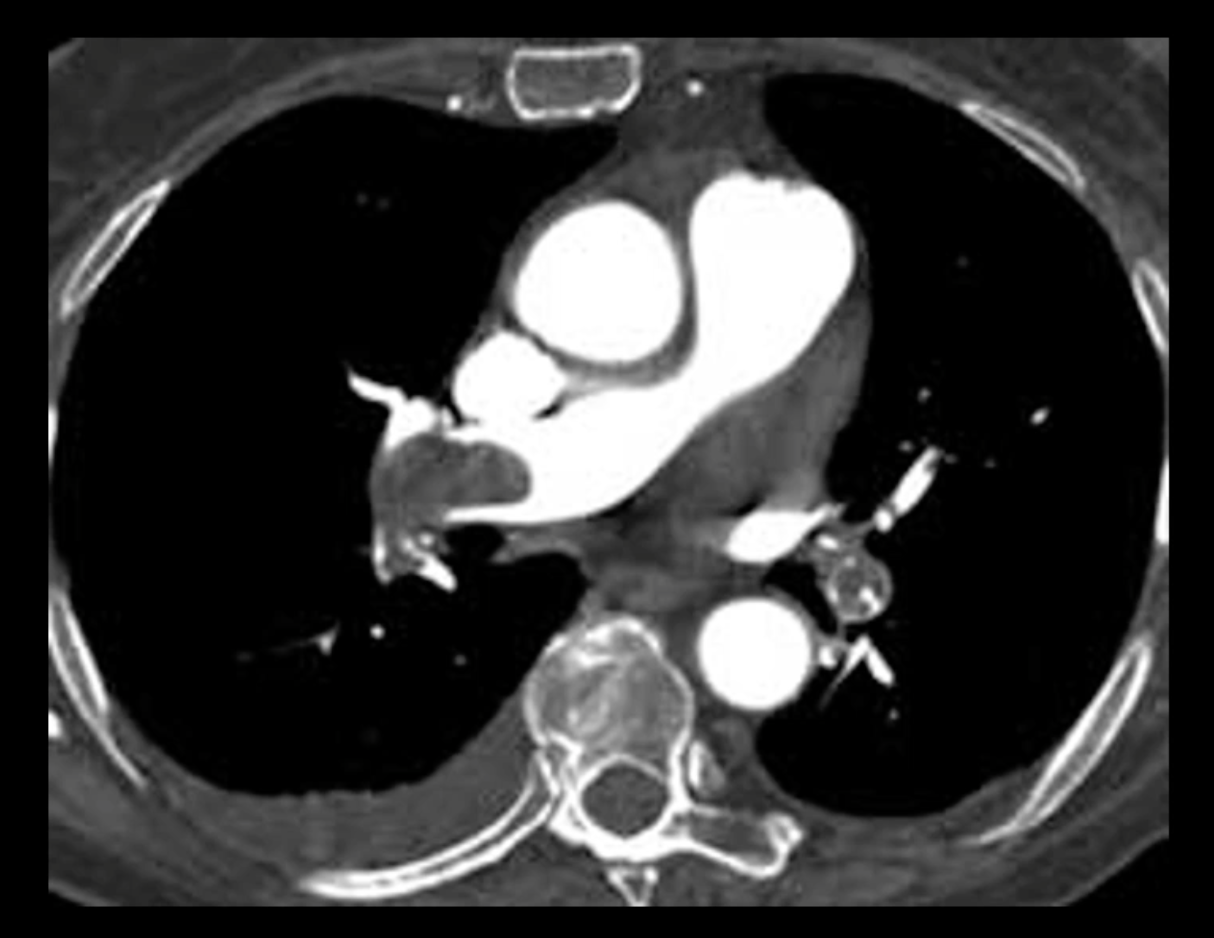

How is CT angiography used to diagnose PE?

A contrast agent is given and when visualized on CT you can see where blockages are. In this image, you can see the gray area that is blocked